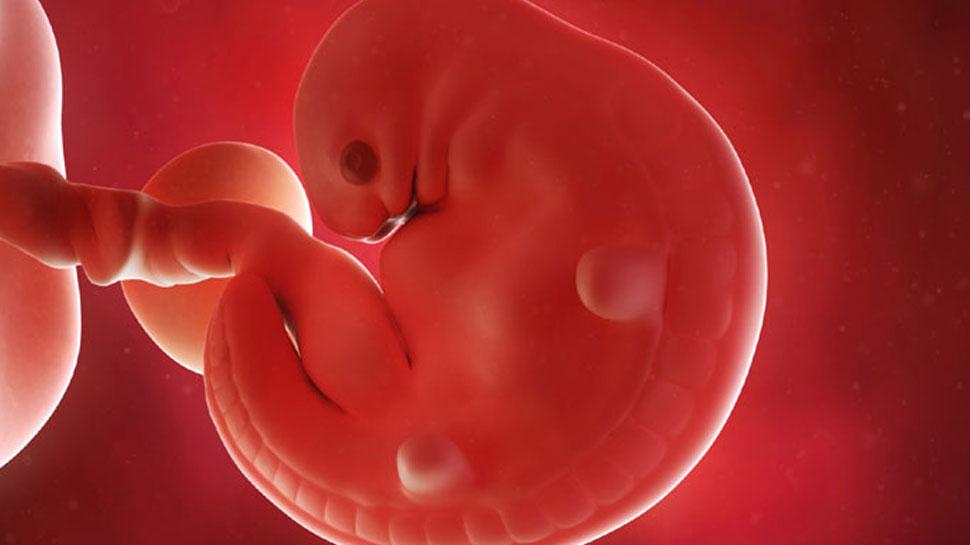

Беременность 6 Недель Развитие Фото

Беременность 6 Недель Развитие Фото 108 фотографий